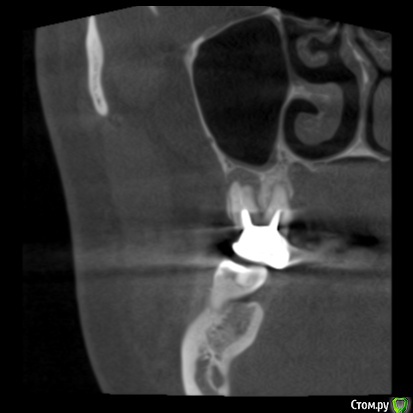

zubovolok Опубликовано 5 октября, 2018 Поделиться Опубликовано 5 октября, 2018 Коллеги подскажите пожалуйста как поступить в данной ситуации, после удаления 1.7и 1.6, чтобы кость восстановилась в хоть каком то объёме в идеале, чтобы избежать синуса? Ссылка на комментарий

zubovolok Опубликовано 5 октября, 2018 Автор Поделиться Опубликовано 5 октября, 2018 Как два сапога - пара.А сейчас какая высота кости?сейчас 10мм Ссылка на комментарий

zubovolok Опубликовано 31 июля, 2019 Автор Поделиться Опубликовано 31 июля, 2019 Подниму тему.вот Удалил 9 месяцев назад после удаления ничего не закладывал, только сгусток. Установил два импланта 1.7- 3.8 на 8 и 1.5-3.4 на 8, имплантиум. Но торк очень трудно получил , очень мягкая кость ( 4-ый тип), коллеги, как получить прогнозируемый, высокий, торк при таком типе кости? Ссылка на комментарий